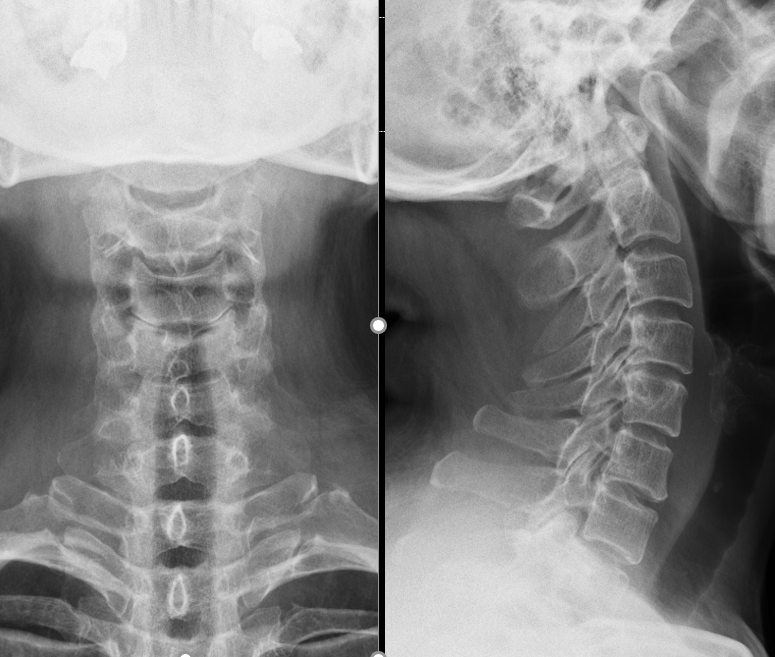

我们看一下患者的影像学资料:

可以看到在颈4/5节段有一明显的致压物向椎管内压迫颈脊髓,并导致脊髓信号发生改变(白色高信号:脊髓损伤的表现)